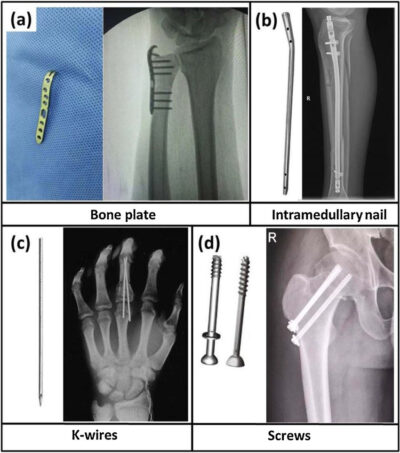

Sometimes hand fracture surgery is required to stabilize and align the bones.

- implant wires

- screws

- plates

in the broken bone to hold the pieces of the fractured bone in place.

After the bone has healed, your surgeon may remove the implants or may leave them in place.